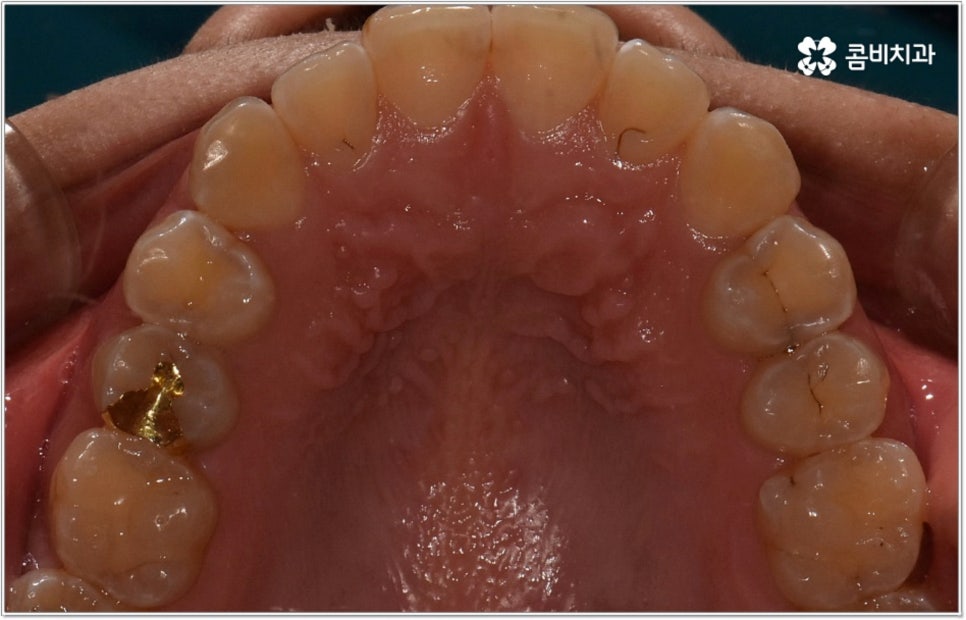

잘 아시다시피 교정이란 치아에 교정 장치 (브라켓) 를 부착하고 와이어에 교정력을 걸어 필요한 방향으로 치아를 이동시킴으로써 고른 치열과 올바른 교합을 가진 정상적인 구강 구조를 회복하는 치과 진료를 의미하는데요, 말씀드린 것처럼 부정교합에는 다양한 형태가 있고 또한 환자분들마다 심각한 정도가 모두 다르기 때문에 현 상태를 면밀하게 체크하고 맞춤 교정 치료 계획을 세우는 것이 무엇보다 중요하다고 할 수 있습니다. 즉 3D CT 와 같은 정밀 진단 장비를 갖추고 있는 치과에서 교정 관련 임상 경험이 풍부한 숙련된 의료진과 함께 치료를 진행하는 것이 필수적이라고 할 수 있어요. 전체 방향 및 세부 플랜을 세울 때 각 환자에 맞게 치아의 이동 속도에 무리가 가지 않도록 하기 위해서 연령이나 발달 상황, 진행 상황을 면밀하게 살펴보는 것이 필요하며 또한 구강 내 공간 유무 및 부정교합 정도에 따라 발치 또는 비발치치아교정 여부를 결정하게 될 거예요.

만약 치아가 이동할 범위를 계산해 봤을 때 공간이 충분하다면 굳이 치아를 뽑지 않고 비발치치아교정 과정으로 치료할 수 있어요. 제일 뒤에 있는 어금니를 더 후방으로 이동시키거나 치간 삭제, 악궁확장장치 등으로 치아 사이를 벌려서 이동 공간을 확보할 수 있으면 비발치치아교정 이 가능한 거예요. 이 때 부정교합이 심각하거나 악골이 치아에 비해 많이 작은 경우, 구조적인 원인을 개선할 필요성이 있는 경우 등 발치 교정을 하는 것이 꼭 필요한 케이스라면 치아를 뽑아주어야 하며, 환자분들의 상황에 따라 다르지만 보통은 소구치를 발치하는 경우가 많이 있습니다.